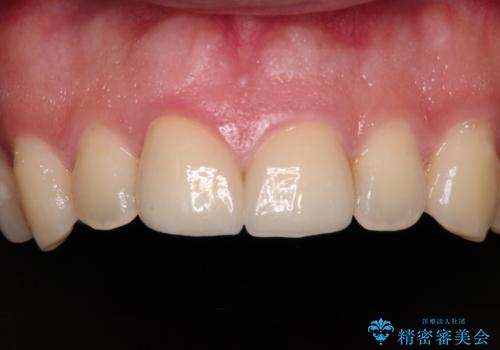

自転車で転んで前歯を損傷 前歯のオールセラミッククラウン

- 自転車で転んで前歯をぶつけたとのことで来院された患者様です。

事故後に受診した病院の歯科にて前歯2本の欠損した部分を修復されておりましたが、見た目が気になるとのことで、オールセラミッククラウンにて補綴治療を行うこととしました。

速やかにオールセラミッククラウンにて補綴治療を行い、数ヶ月後に再度神経組織の状態を確認して、失活しているようであれば根管治療を行うこととしました。